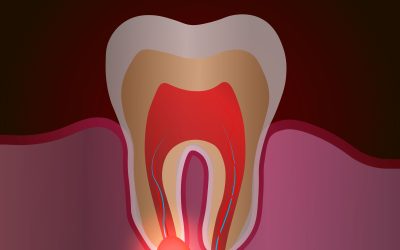

Come si svolge un’apicectomia: fasi, benefici e decorso

L’apicectomia è un intervento chirurgico odontoiatrico che permette di trattare infezioni persistenti alla radice del dente senza intervenire dalla corona. Il dentista accede direttamente all’apice radicolare incidendo la gengiva, rimuove la parte infetta e deterge accuratamente il canale. Nei giorni successivi possono comparire lieve dolore, gonfiore o difficoltà nella masticazione, facilmente gestibili seguendo le indicazioni del dentista e assumendo i farmaci prescritti.